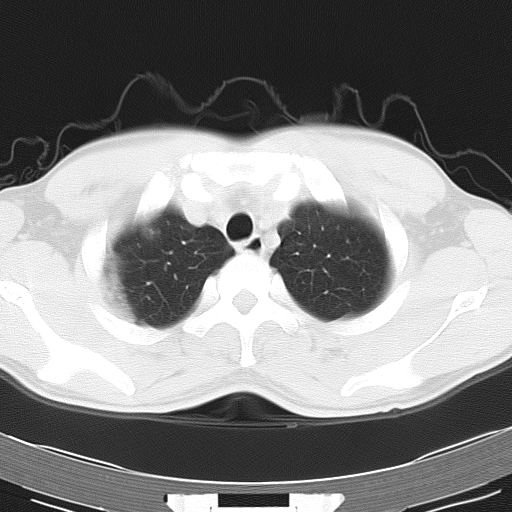

两上肺磨玻璃样改变,均位于肺外周,考虑1、肺泡蛋白沉着症?2、肺泡炎?请询问有无养鸟史 3、脱屑性间质性肺炎?建议进一步检查、复查随访

两上肺的ggo,靠近胸膜,不是以节段分布,青年男性,个人意见为吸入性的真菌感染可能为大------------呼吸内科医生

两肺上叶近胸膜磨玻璃样阴影,考虑1、炎性病变。 。2、过敏性炎症?

病灶特点:

分布在肺野的外带,病灶边缘清楚,病灶以磨玻璃影为主夹杂少许纤维状高密度影

支持zhangzhongshou主任,考虑蛋白沉着症可能性大

(1)斑片状磨玻璃影:指肺野密度朦胧增加,内可见肺血管纹理影,系肺泡腔内充满低密度的磷脂蛋白物质所致。

(2)其内部小叶间隔或小叶内间隔增厚所形成的网格状影,为小叶间隔水肿、肺泡壁内淋巴细胞和巨噬细胞浸润以及小叶内淋巴管扩张的缘故。

(3)病灶边缘清楚,呈地图样分布于肺野外围或肺门及中央区。

肺泡蛋白沉积症;胸膜下区磨玻璃样,实变区见纹理走形,地图样改变。做mri。

据报告﹐自7~8个月的婴儿至72岁的老人均有患肺泡蛋白沉积症者﹐但以30~50岁者居多。男性约为女性的3倍。鉴于约半数病人经常接触各种粉尘或有害气体﹐且以硅尘长期给鼠吸入﹐可使动物患肺泡蛋白沉积症﹐故认为本病可能是肺泡对化学性刺激的非特异性反应,导致肺泡巨噬细胞分解,产生pas阳性蛋白质。

该患者男性,34岁,进一步追问病史,该人系矿砂堆场码头工人,长期粉尘环境下工作。--这条病史符合以上特点。

ct表现 (1)中央型:表现为蝶翼状浸润性阴影对称分布于两侧肺门周围,其内可见支气管充气征,病变区与正常肺组织分界清楚。(2)外围型:表现为多发性条片状、斑片状及斑块状高密度影,弥散、对称或不对称分布于两肺或一侧肺外围部位。病变区与正常肺组织及脏层胸膜面分界清晰,呈地图样改变。hrct可显示小叶间隔增厚及肺小叶内淡淡的密度增高影等细微结构,同时易发现肺大疱、肺气囊及节段性肺不张。

再仔细阅读该病人的ct片,我们不难发现,病例所表现的正是外围型的肺泡蛋白沉积症表现,即:为多发性条片状、斑片状及斑块状高密度影,弥散、对称或不对称分布于两肺或一侧肺外围部位。病变区与正常肺组织及脏层胸膜面分界清晰,呈地图样改变。

所以,我本人的意见也是趋向于肺泡蛋白沉积症的诊断,尽管最后诊断还是要根据支气管肺泡灌洗物检查或经纤支镜或剖胸活检作出病理诊断。或痰液检验:咳出的痰经80%乙醇固定,pas染色有15%阳性的脂质。